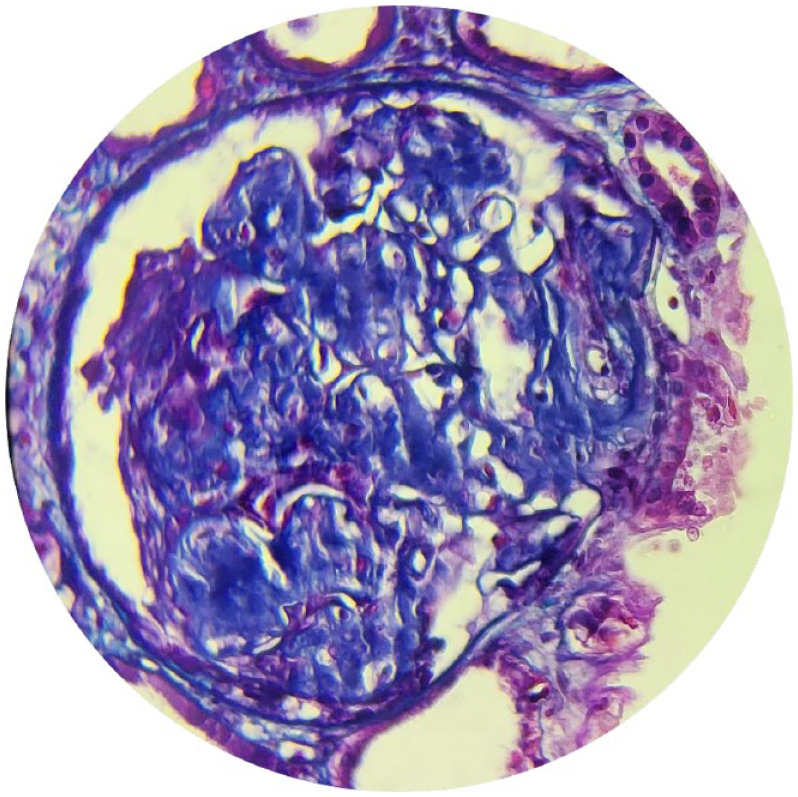

Familial Mediterranean fever (FMF) is an autosomal recessive disorder, particularly common in the Mediterranean area. Mutations in the MEVF gene cause it. AA Amyloidosis is the most severe complication of FMF leading to chronic renal failure. We describe a rare pediatric case of a phenotype I familial Mediterranean fever with V726A heterozygous mutation. The diagnosis was made at chronic kidney disease. We discuss through this case the importance of the early diagnosis of FMF heterozygous children which is not usually evident in some phenotypes. It will surely avoid fatal complications, inappropriate therapeutic approaches and higher healthcare costs.

Abstract Image